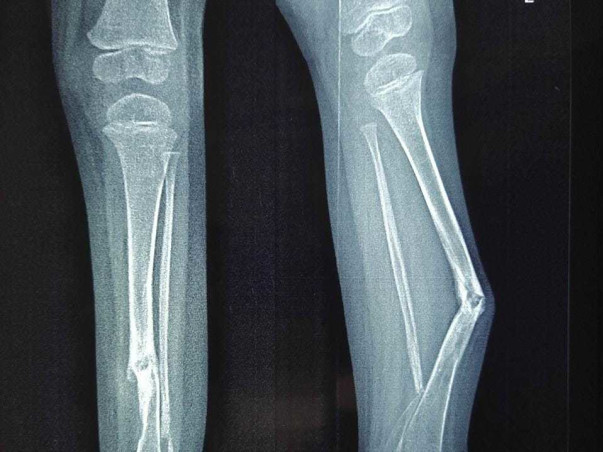

2 Years Old Aahil Iyad Needs Your Help To Recover From Bilateral Congenital Pseudarthrosis Of Tibia

Hi, my name is Wajid As many friends and family know my son Aahil Iyad was born with a rare genetic condition called Neurofibromatosis-Type-1 and as part of its characteristics he is now facing Bilateral Congenital pseudarthrosis of the tibia in both legs, a very rare condition that affects 1 in 10Lakh people. once a fracture has occurred its healing capacity is almost non-existent.

Unfortunately, when Aahil was 9 months old he fractured his left leg, ever since then Doctors have recommended to wear protective braces for both legs and is unable to walk as normal kids of his age do…although he is very afraid of Doctors we know he is in need of major surgery and hopes this surgery heals him.

Here in India we have consulted various Hospitals such Rainbow, Sunshine, Vijaya, NIMS, Ganga Hospital Coimbatore, CMC hospital in Vellore, BIRDS hospital Tirupathi, Mannheim Medical University Germany, Dr. med. Stefan Schmitz Clinic Ludwigshafen Germany and for majority of Doctors this condition was new and cannot help or guarantee his healing. I did a lot of research and joined a FB group where I found hope with Dr. Dror Paley, Paley Ortho and Spine Institute, Poland  that has 100% success rate in healing Tibia and Fibula bones with X-Union technique. The insurance that my son is covered has denied treatment as it is of a congenital disorder. However even after treatment my son has to undergo surgery for every 4-5 years in order to replace the rod that would be inserted in his limb from Knee to foot. Unfortunately even the right leg is in pre-fracture stage and is also in need of immediate attention.